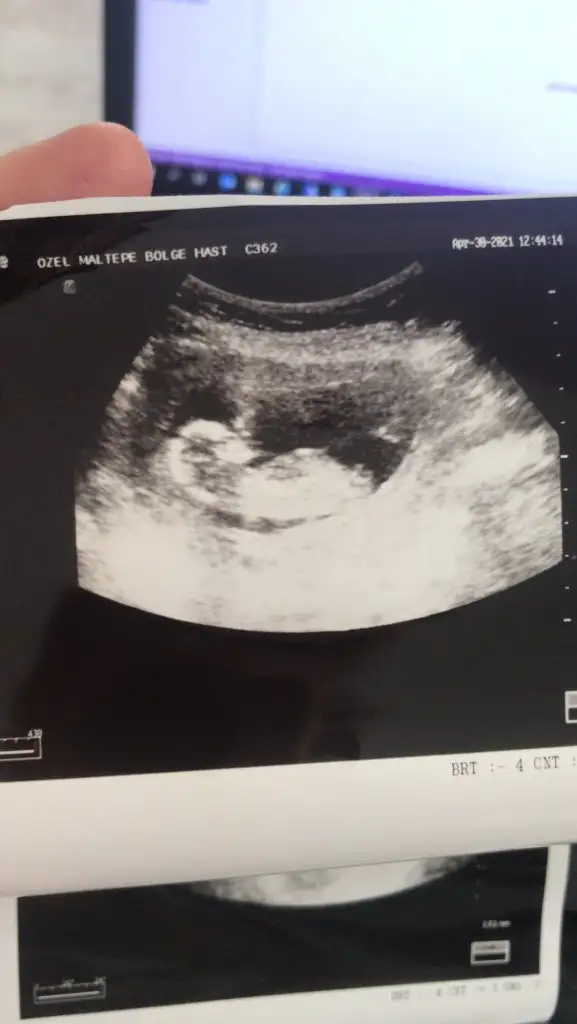

Merhaba lütfen tahmin yaparmısınız 2 yıl öncede yapmıştınız tutmuştu :)))

Eklentiler

• 20210502_063913.webp

20210502_063913.webp

14,9 KB · Görüntüleme: 58

• 20210502_063853.webp

20210502_063853.webp

13,6 KB · Görüntüleme: 62